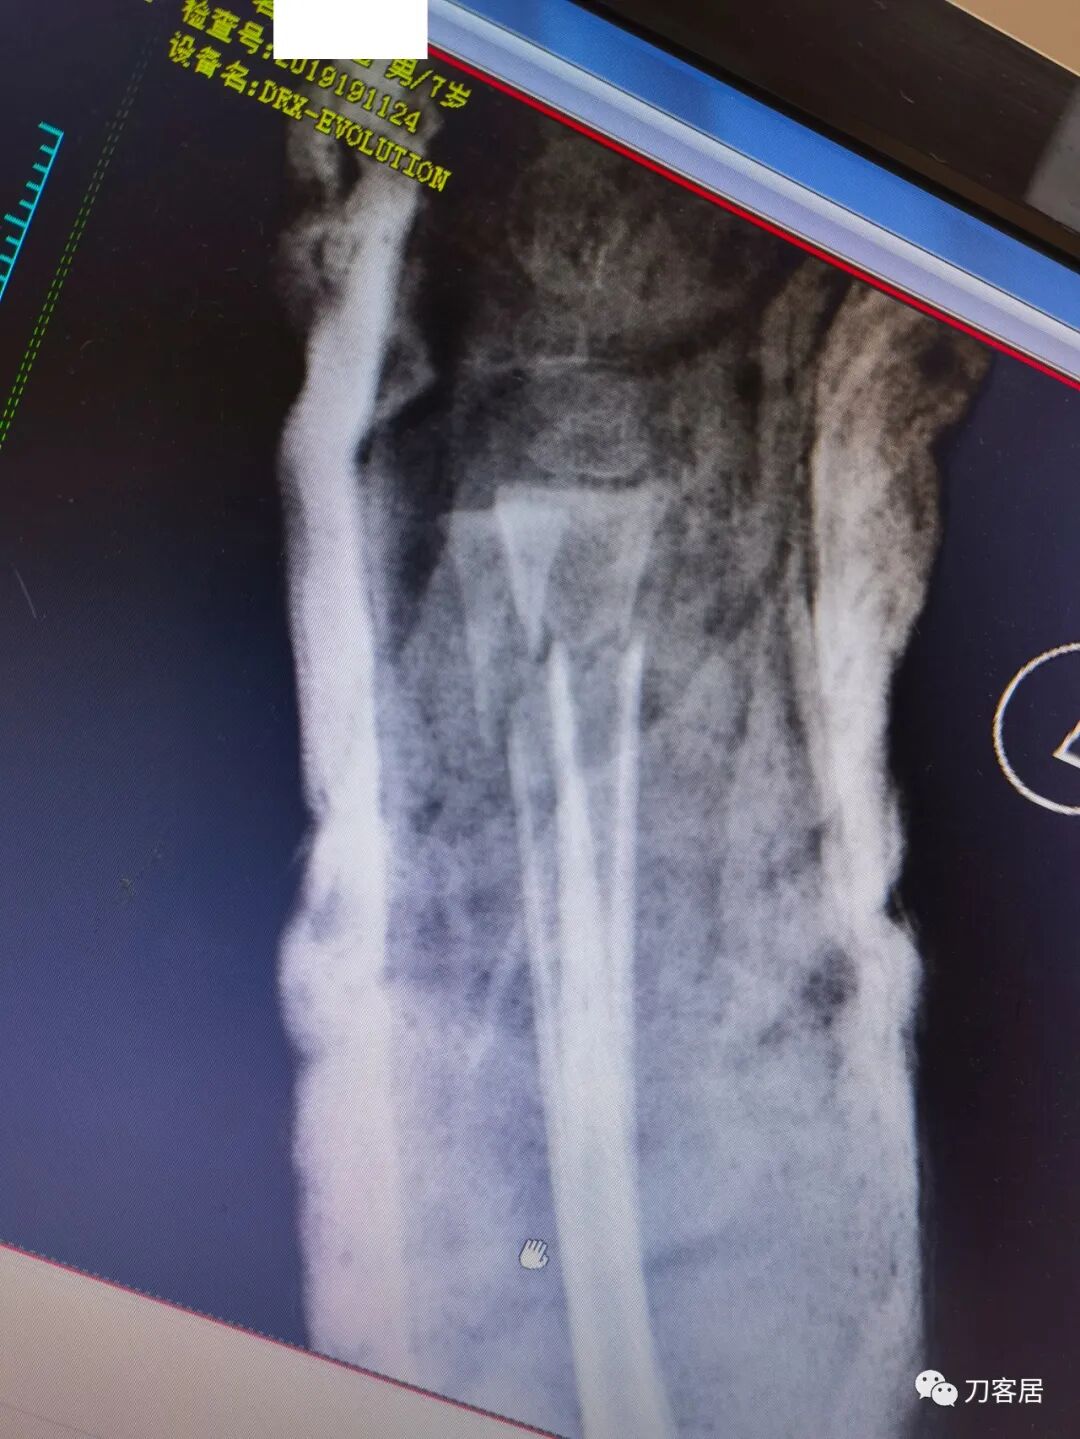

下面是这个6岁孩子,尺桡骨远端双骨折的术前及术后片子和外观照片。

1.  这是一个很简单的6岁儿童无移位的尺桡骨远端骨折。没有皮肤损伤,没有移位,没有骨折碎块儿。

2.  这个骨折处理起来也很简单,单纯的打石膏托或者中医的小夹板,或者正规的包括腕关节和肘关节的管型石膏外固定4周即可治愈该骨折。实在不行,如果这个孩子比较听话,不太调皮的话,用一本书,一个三角巾悬吊固定4周,都可以治愈该骨折。但是给这个患者用外固定架做了手术,而且桡骨远端的几颗克氏针距离骨折线太近,其中一枚克氏针进入到骨折间隙内。从这个术中图片来看,术者的外固定手术技术也有待于进一步的提高。毕竟术者应该还很年轻。从X线片来看,前臂及手的尺侧有不透光影,应该还使用了外固定石膏绷带托,而且我猜测应该是高分子的石膏绷带托,这个是纯属猜测,不一定是对的,不过如何解释前臂尺侧的不透光影呢?如果真是用了石膏绷带外固定的话,那为啥要做手术呢?外固定架术后就不该再用石膏绷带托辅助了。